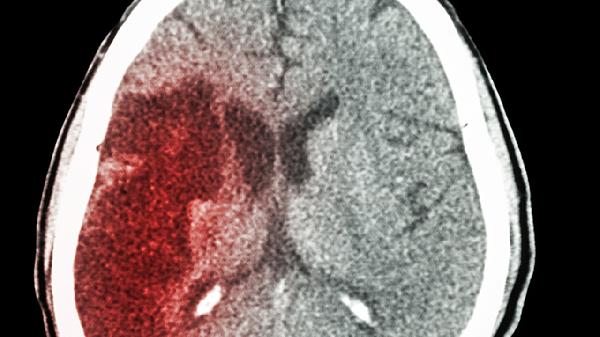

外伤导致脑出血后可能留下哪些后遗症

外伤性脑出血可能留下多种后遗症,包括运动功能受限、语言能力下降、认知功能减弱、情绪行为异常以及癫痫发作等。这种类型的脑出血通常由头部受到外力冲击引起,比如交通事故、高空坠落或暴力伤害,其严重程度取决于出血的范围、位置以及治疗是否及时。

对于外伤性脑出血的后遗症,康复过程需要多个专业领域共同参与。除了按时服药外,建议保持清淡饮食以控制血压,每天进行半小时左右的有氧运动,帮助神经功能恢复。家属要协助患者养成良好的作息习惯,定期复查头颅CT了解恢复状况。一旦发现头痛加重或意识状态变化,应尽快送医处理。